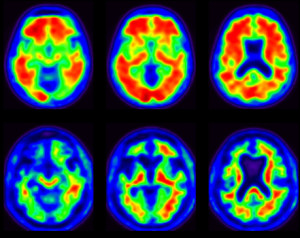

We are proud to be a site for the Imaging Dementia - Evidence for Amyloid Scanning (IDEAS) Study. This $100 million study will be the largest of its kind, eventually enrolling over 18,000 patients to assess the clinical utility of amyloid PET scans for guiding medical management and improving outcomes in patients suffering from cognitive impairment of uncertain cause.